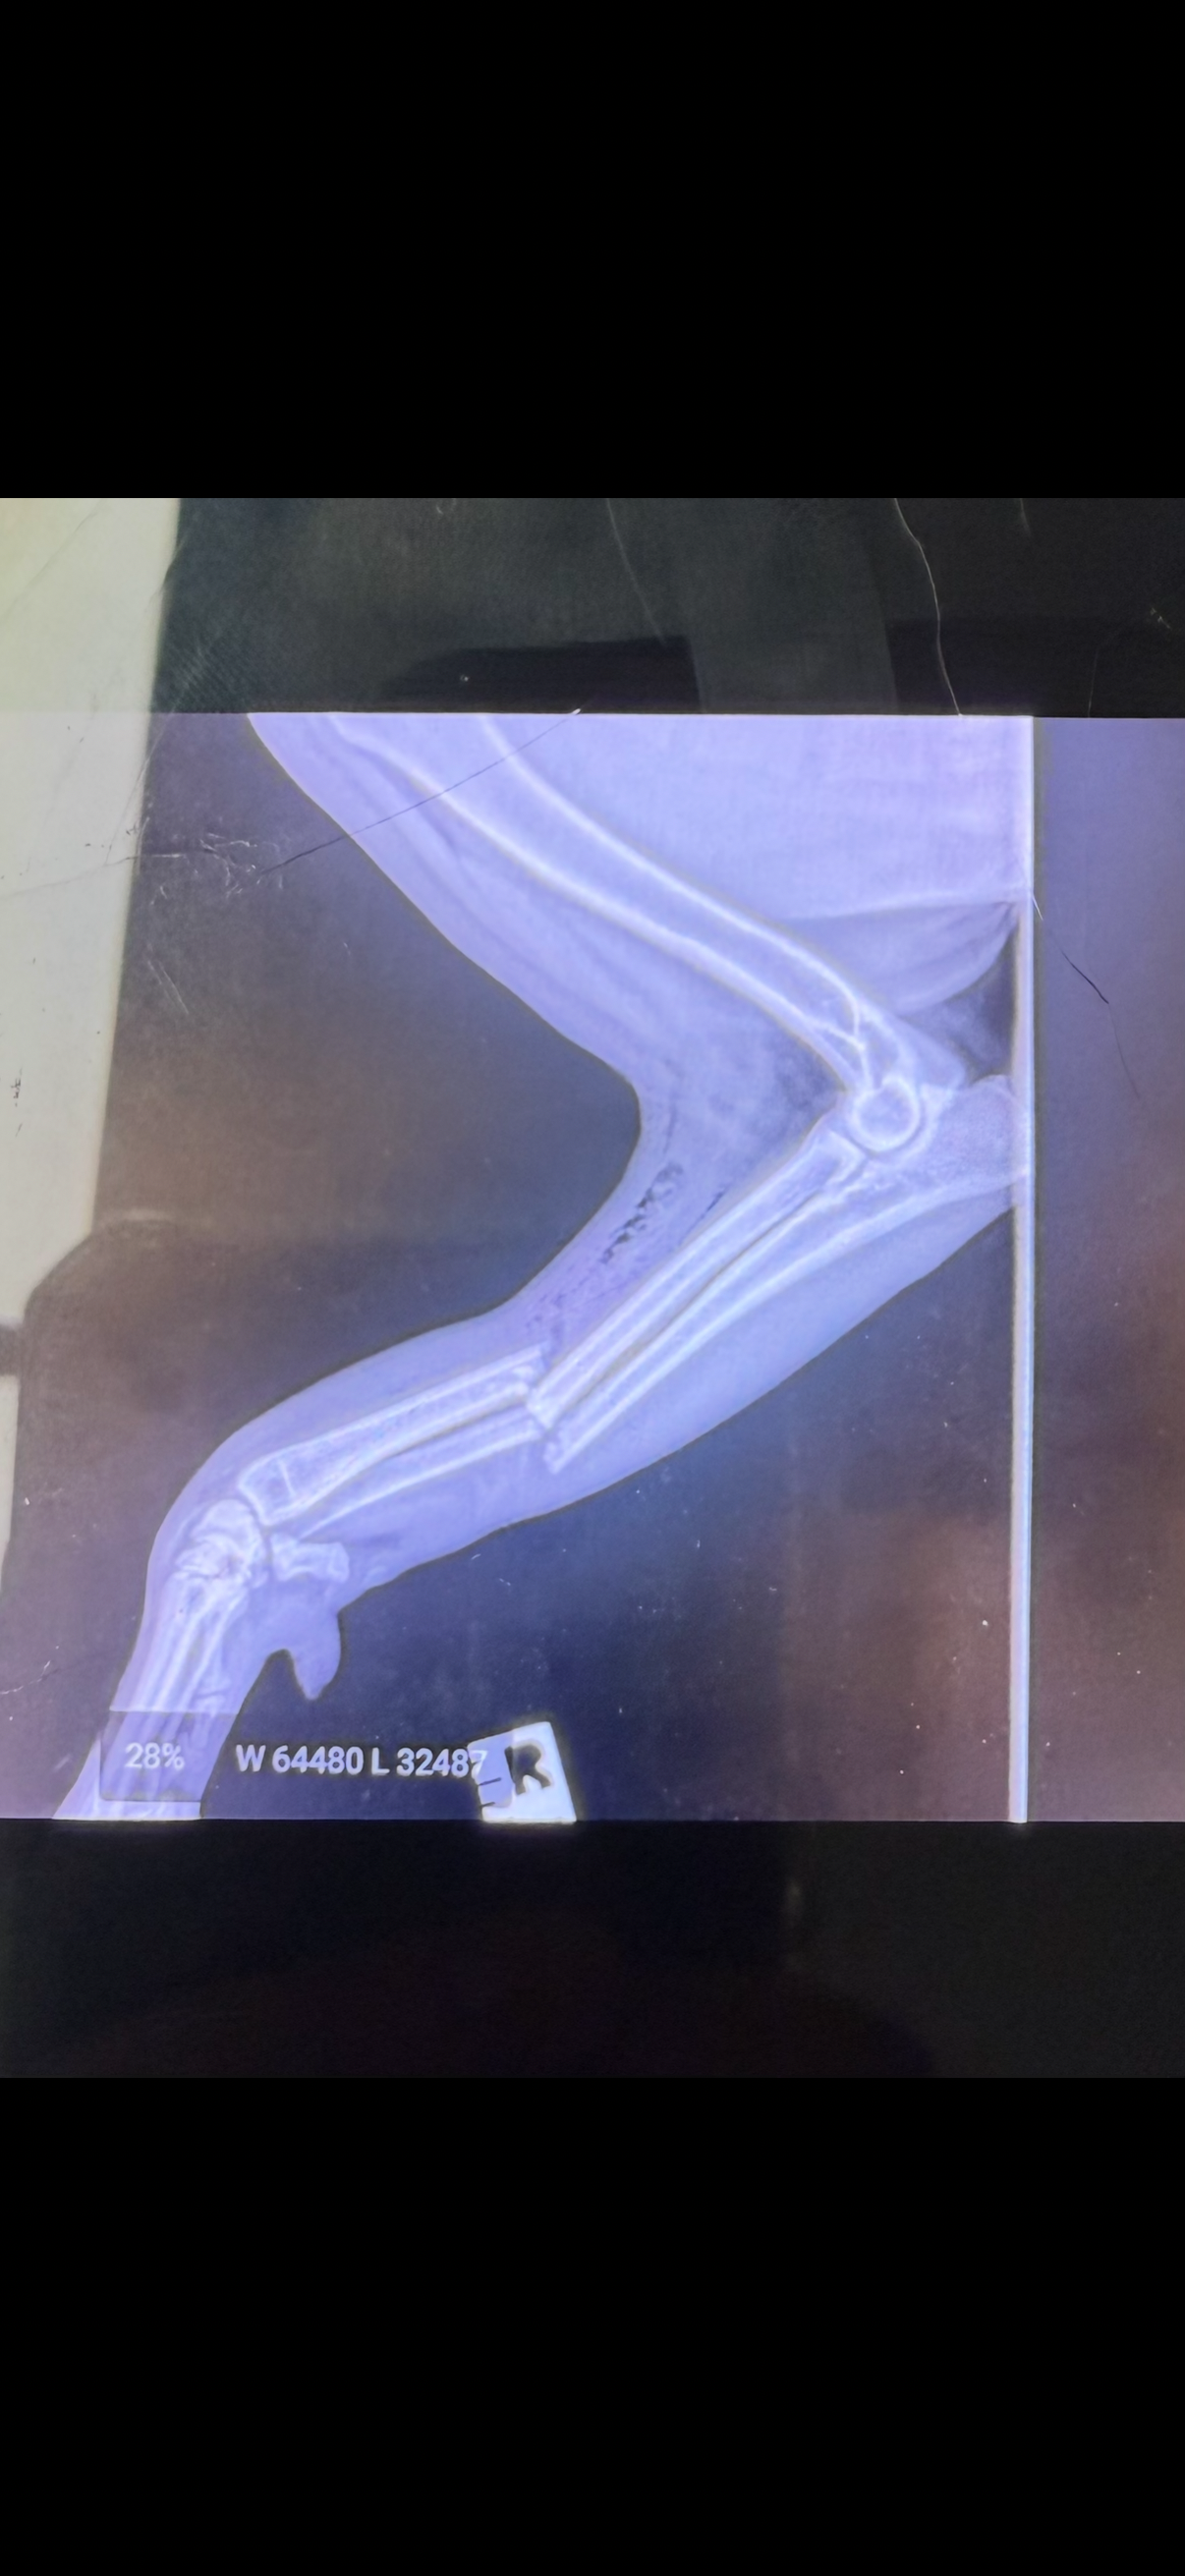

* A severely broken leg

* Multiple deep wounds

The vets have told us she needs extensive treatments, surgeries, and immediate ongoing care.

Her medical costs are already around 9,000$, and could reach $10,000+ depending on surgery and recovery.

Her splint change is already a day late, must be replaced — it’s urgent, and without it her leg could get worse — but I simply cannot afford it right now.